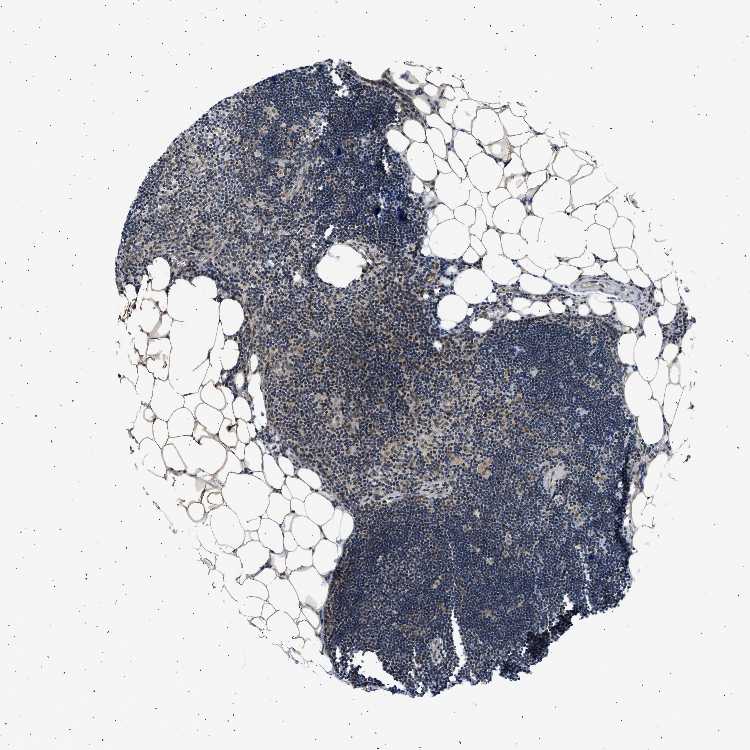

TISSUE PRIMARY DATA LYMPH NODE Show tissue menu

Lymph node

Lymphoid tissue

LYMPH NODE - Expression summary

LYMPH NODE - Antibody stainingi

Antibody staining in the annotated cell types in the current human tissue is reported as not detected, low, medium, or high, based on conventional immunohistochemistry profiling in selected tissues. This score is based on the combination of the staining intensity and fraction of stained cells.

Each image is clickable and will lead to virtual microscopy that enables deeper exploration of all samples and also displays staining intensity scores, fraction scores and subcellular localization as well as patient and tissue information for each sample.

Antibody HPA062997Antibody CAB014874

Germinal center cells MediumHigh

Non-germinal center cells MediumHigh